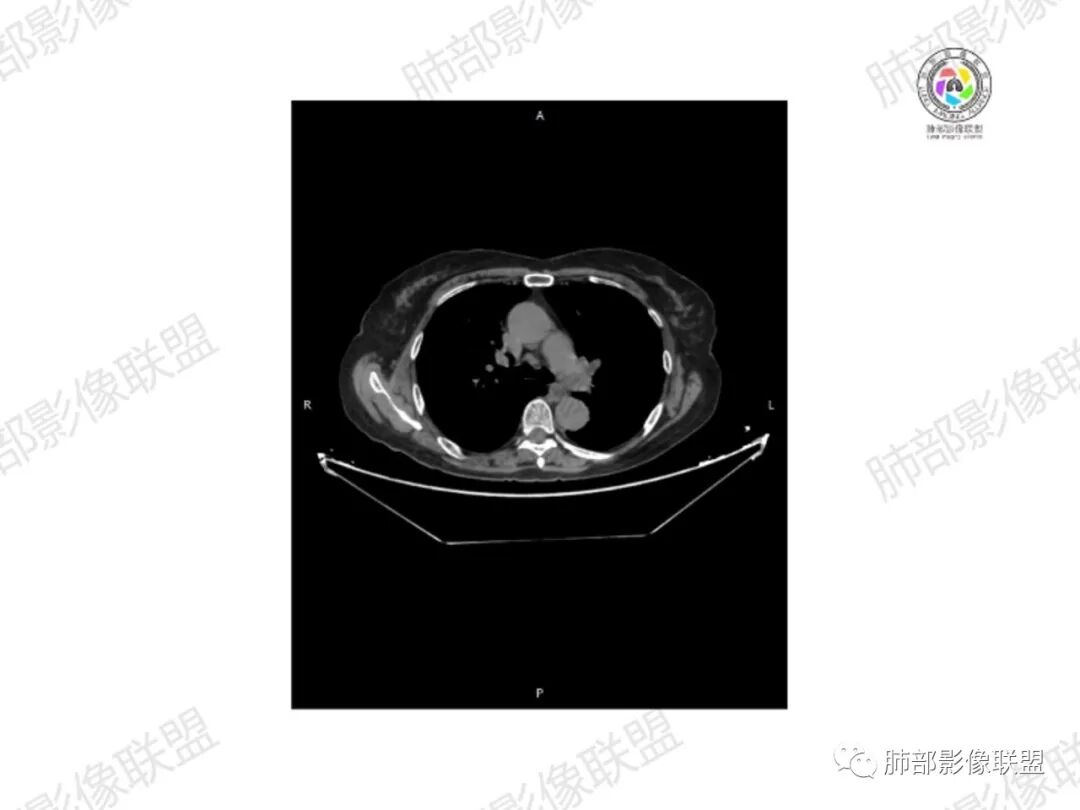

5.双肺多发类圆形结节影,边界清楚,随机分布,其间多见钙化密度影。

6.双肺门及纵隔未见肿大淋巴结。

7.扫描范围内双侧乳腺未见明显块影。

3.双肺病灶符合转移瘤,伴有中央部分钙化者也以骨肉瘤转移较为多见。